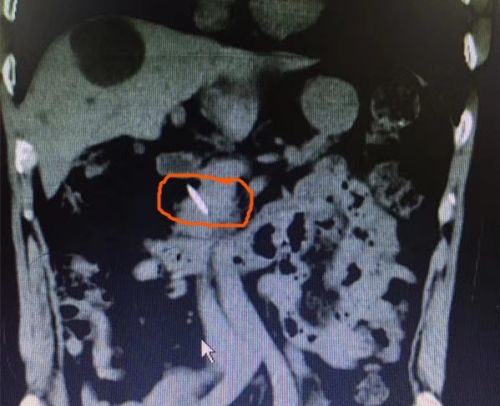

腹部CT可以看到金属异物戳破肠壁。

随即,老人被收入结直肠肛门外科病房,并完善腹部CT。结果又吓出大家一身冷汗,CT显示,异物位于胰腺后方,距离肠系膜上静脉仅几毫米,随时可能刺破血管,给患者带来生命危险。医生和家属反复询问陈爷爷是否误服过什么东西,但老人表示毫无印象。